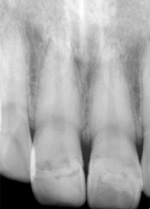

![]() |

治療後のX線写真。歯の神経は生きてます。 |